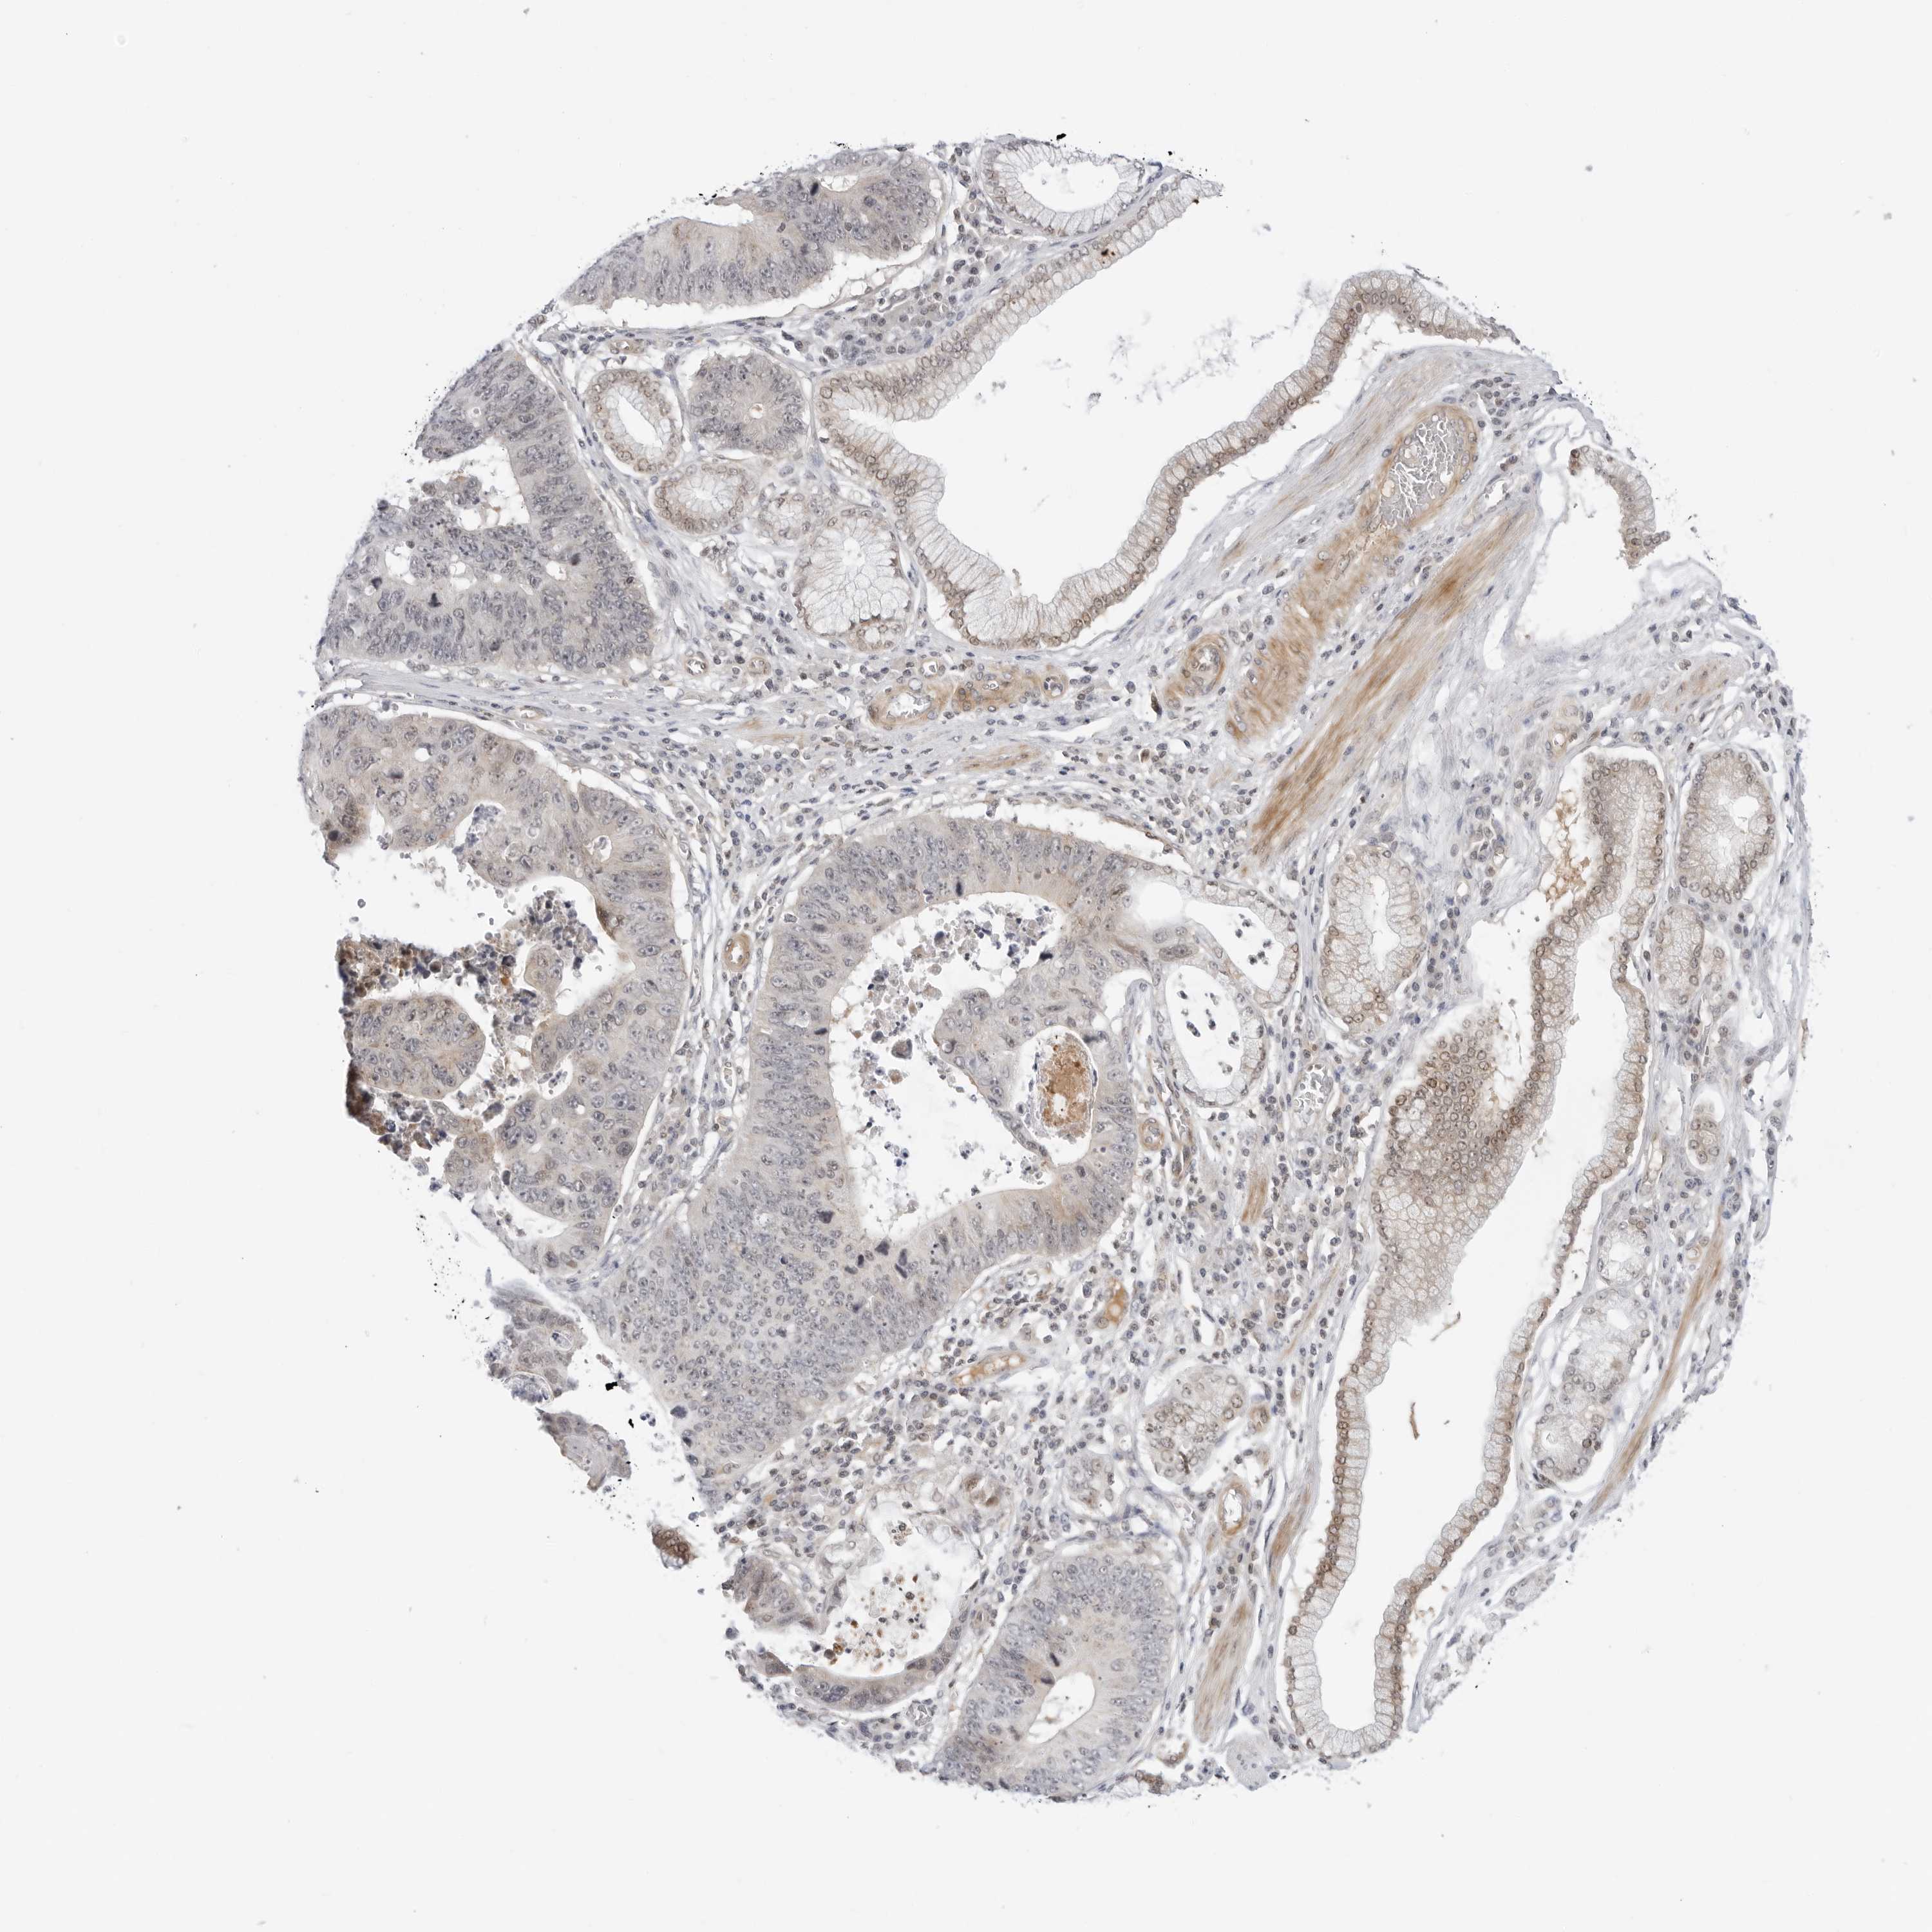

STOMACH CANCER - Protein expressioni

A mouse-over function shows sample information and annotation data. Click on an image to view it in a full screen mode. Samples can be filtered based on level of antibody staining by selecting one or several of the following categories: high, medium, low and not detected. The assay and annotation is described here.

Note that samples used for immunohistochemistry by the Human Protein Atlas do not correspond to samples in the TCGA dataset.

Antibody stainingi

Antibody staining in the annotated cell types in the current human tissue is reported as not detected, low, medium, or high, based on conventional immunohistochemistry profiling in selected tissues. This score is based on the combination of the staining intensity and fraction of stained cells.

Each image is clickable and will lead to virtual microscopy that enables deeper exploration of all samples and also displays staining intensity scores, fraction scores and subcellular localization as well as patient and tissue information for each sample.

Antibody HPA026698

Antibody HPA026704

Antibody HPA026705

Staining

High

Medium

Low

Not detected

Intensity

Strong

Moderate

Weak

Negative

Quantity

>75%

75%-25%

<25%

None

Location

Nuclear

Cytoplasmic/membranous

Cytoplasmic/membranous,nuclear

Adenocarcinoma, NOS